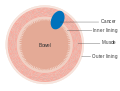

Dukes stage A bowel cancer; the cancer is only in the inner lining of the bowel. Dukes stage B bowel cancer; the cancer has invaded the muscle.

Dukes stage B bowel cancer; the cancer has invaded the muscle. Dukes stage C bowel cancer; the cancer has invaded the nearby lymph nodes.